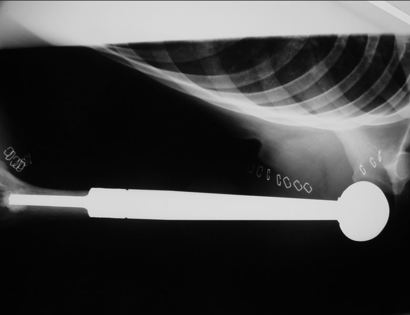

A total humerus prosthetic replacement is a procedure that involves removing a tumor, usually malignant or benign aggressive, of the entire arm bone/humerus and in most instances replacing the bone with a special customizable total humerus tumor prosthesis.

The tumor prosthesis is inserted. This prosthesis is sized and built during the surgical procedure then implanted. Then the prosthesis is cemented into the bone and is safely secured in place.